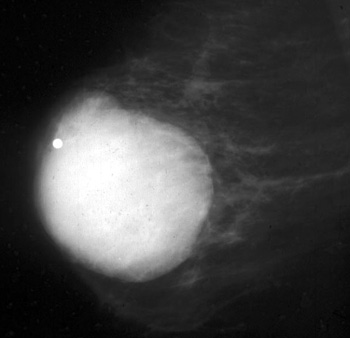

عند النساء الشابات، قد يكون الثدي كثيفًا.

مع تقدم المرأة في العمر، يحدث ارتشاح دهني للثدي يرتبط بضمور الأنسجة الغدية.

تكون الدهون شفافة ومظلمة في تصوير الثدي بالأشعة السينية.

الأنسجة الغدية والسرطانية كثيفة وبيضاء في تصوير الثدي…